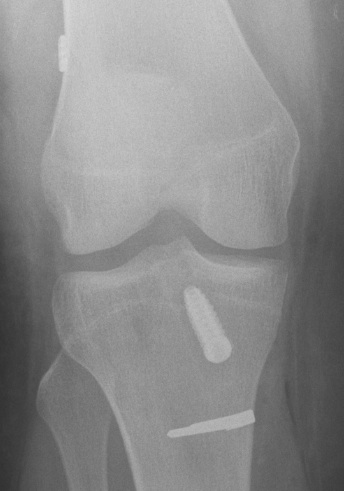

Tibial tunnel

Use drill guide set at 55o

- use < 55o if short graft

- entry medially through hamstring incision

- set for wire to exit either tip or elbow

- anterior to PCL

- posterior half of ACL stump

- identify medial tibial spine and anterior horn of lateral meniscus

- 2/3 along this line towards medial tibial spine

- pass beath wire

- drill tunnel line to line

2 x RCI screws

Tunnels

- as above

Femoral tunnel

- pass beath pin

- drill line to line for graft size

- usually 25 mm long